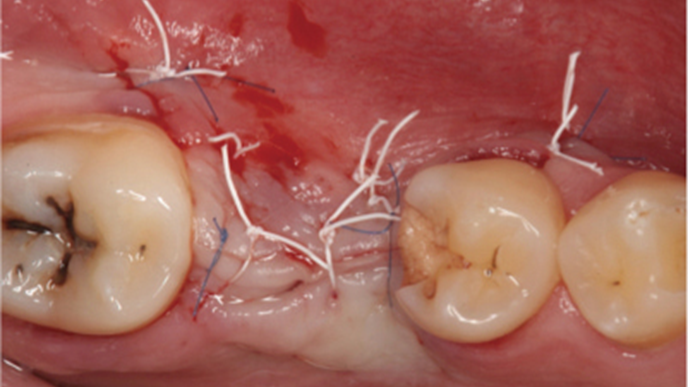

Clinical case: # 46 implant placement & GBR using i-Gen membrane for significant vertical resorption & mixed bone defect

- Courtesy of Dr. Iulian Filipov, Romania -

AnyRidge, mandibular posterior, i-Gen, resorption, bone defect, bone regeneration, space management, #46, GBR, Dr. Iulian Filipov

AnyRidge implant system, i-Gen